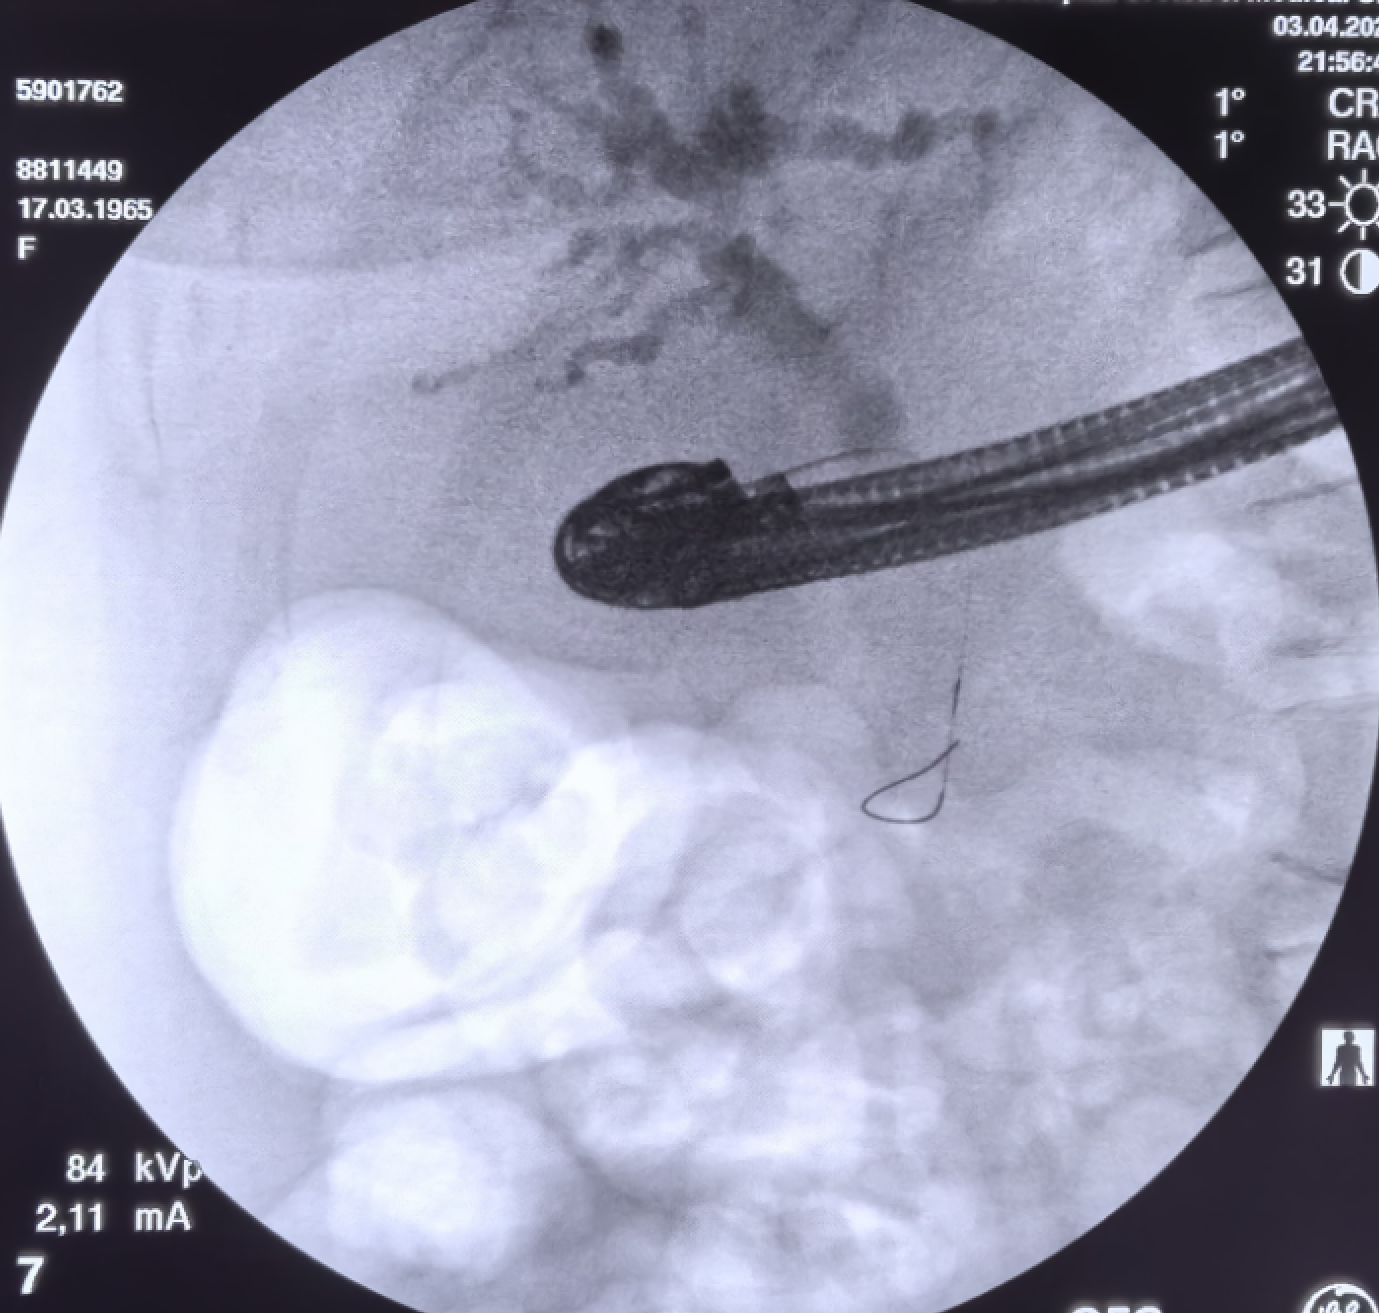

一例假性囊肿,囊肿较大,EUS下看着囊壁和胃壁非常近

囊肿切开刀切开后,置入双导丝

可是扩张的时候需要注意了,内镜下扩张水囊在胃腔不长

所以现在只扩开了胃壁

调整水囊进入囊肿,再次扩张